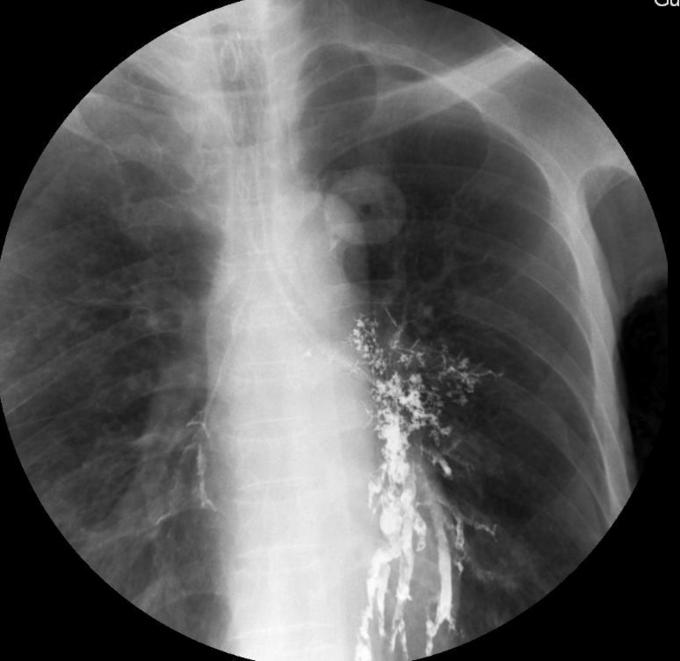

钡餐误吸

男性,61岁吞咽困难1月 进行性吞咽困难,无饮水呛咳,无发热,无咳嗽 咳痰

患者白日行钡餐检查,夜间出现呼吸困难,血氧饱和度下降,考虑存在1型呼吸衰竭 讨论: 1.目前针对钡餐误吸性肺炎的治疗措施哪些有意? 2.如何预防本次事件?